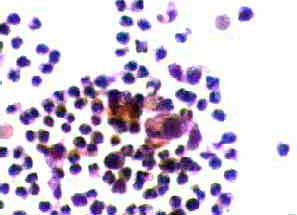

Aσθενής 45 ετών, με γνωστή παρουσία πολλαπλών κύστεων και στους δύο μαστούς εδώ και πολλά χρόνια.. Επώδυνη κύστη διαμέτρου 4 εκ. στον αριστερό μαστό. Κάτω από υπερηχογραφικό έλεγχο παρακέντηση και αφαίρεση περίπου 20 κ. εκ. κιτρινωπού υγρού.